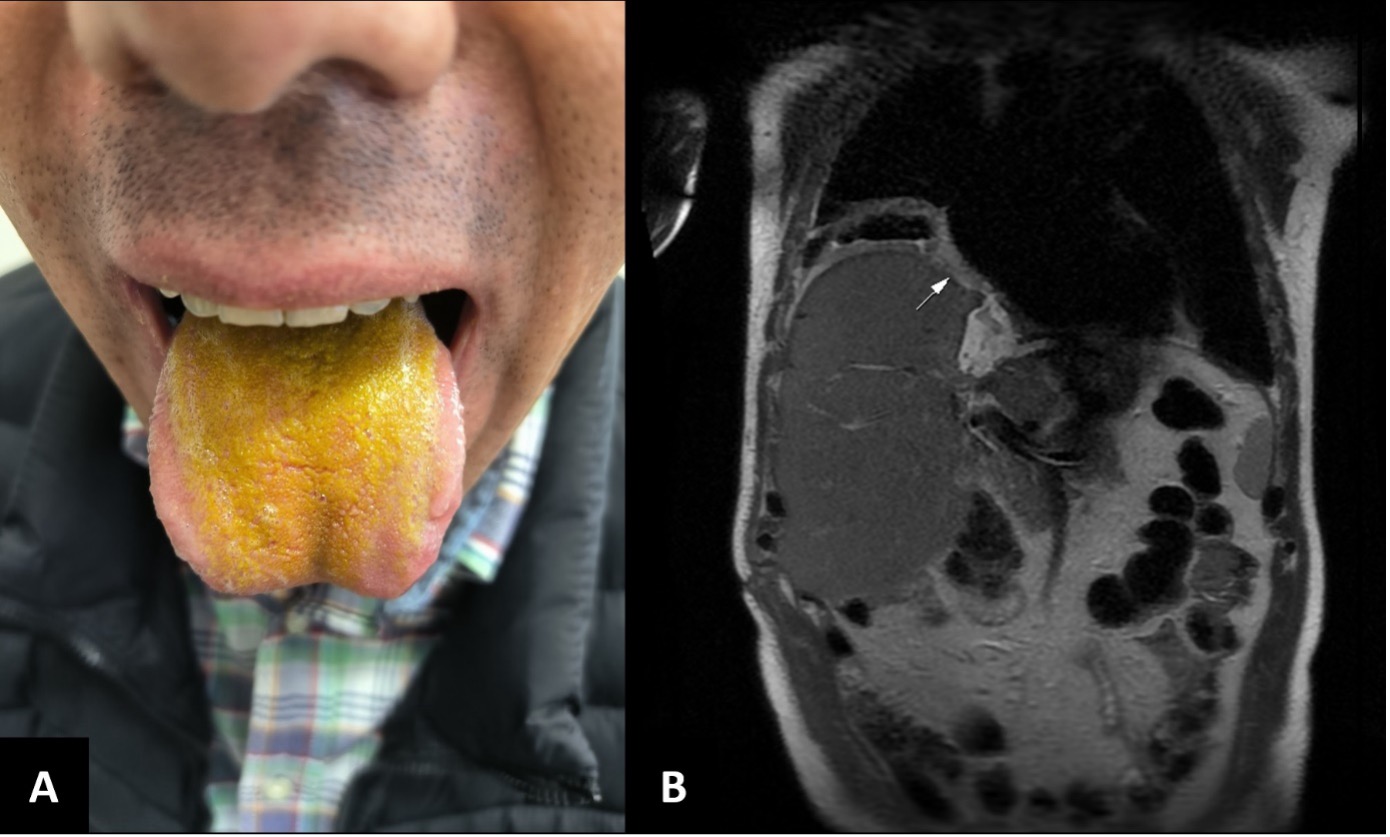

A Unique Tongue Presentation Revealing a Bronchobiliary Fistula

Adil Zegmout, Youssef Zemmez, Hanane Asri, Hicham Souhi, Hanane El Ouazzani, Ismail Abderrahmane Rhorfi